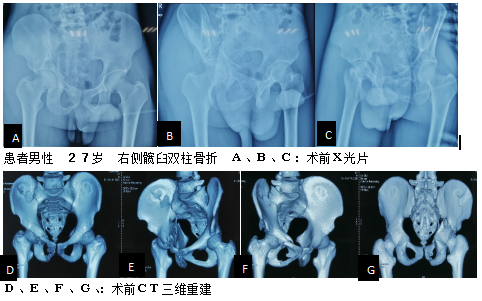

以下图片是我科骨盆髋臼骨折腹直肌外侧入路手术技术的两例患者资料。(骨二科)

实例二